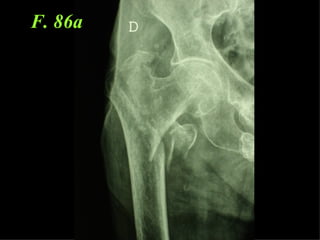

F. 86a

La placca a compressione percutanea (PC.C.P.) di Gotfried è un mezzo di sintesi studiato per assicurare un “impattamento controllato” delle fratture pertrocanteriche grazie alle due viti telescopiche prossimali che garantiscono una ottima stabilità rotazionale

Tradizionalmente si ritiene importante per la stabilità delle fratture pertrocanteriche l’integrità della parte mediale della metafisi prossimale del femore

In realtà la zona più importante per la ricostruzione di questo tipo di fratture è il muro laterale contro il quale si impatta il frammento metaepifisario mediale

Se il muro laterale è rotto o viene lesionato durante la sintesi , come spesso accade in fase di applicazione della vite cefalica dei chiodi endomidollari o della vite-placca, andremo incontro al collasso della frattura e ad un conseguente lungo periodo di impotenza funzionale

Con la placca di Gotfried non si è mai riscontrato un danno iatrogeno del muro laterale e nessun collasso della frattura.Ciò è dovuto al fatto che i fori per l’applicazione delle due viti prossimali sono di piccolo diametro (9 mm) rispetto ai 16-32 mm necessari per introdurre la vite cefalica di un chiodo endomidollare o di una vite-placca a compressione.

La placca PC.C.P. viene inoltre applicata per via percutanea attraverso due piccole incisioni ottenendo in tal modo un minimo trauma chirurgico ed una  perdita di sangue estremamente ridotta in pazienti che per l’età  sono già in condizioni  critiche

Dal Gennaio 2005 ad Agosto 2006 110  placche di Gotfried Età media  : 78 anni (range 29-94) Tempo chirurgico: 30 minuti (range 12-45) IMMEDIATA CONCESSIONE DEL CARICO